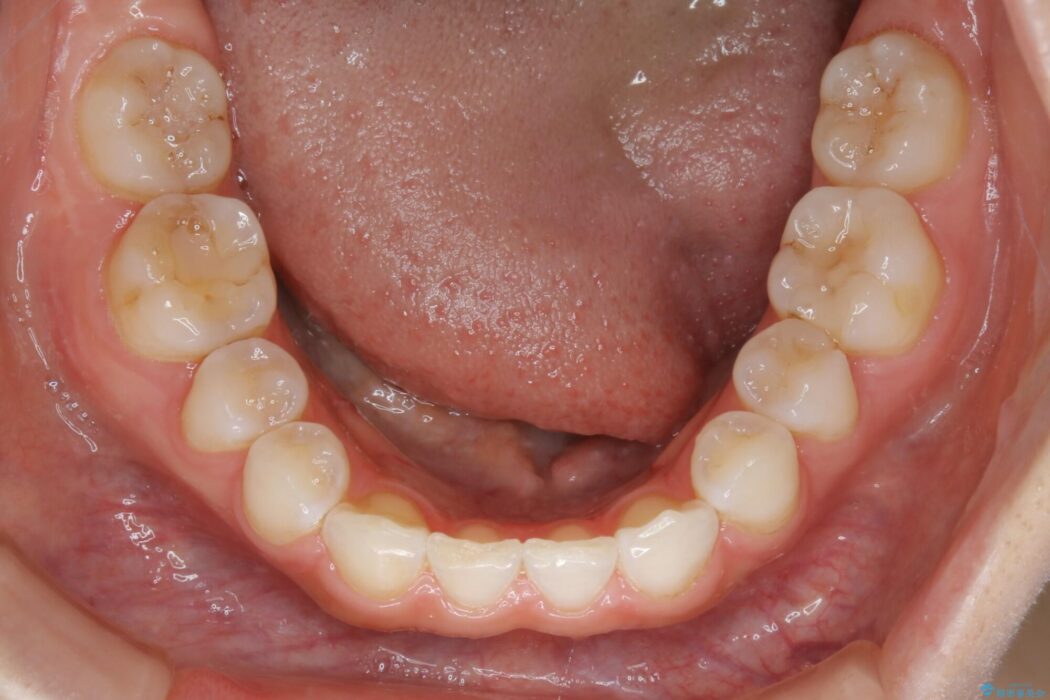

診査したところ叢生だけでなく生まれつき永久歯の欠損、いわゆる先天欠如により歯の本数が少ないため噛み合わせなどにも影響が出ている状態でした。

特殊な状況からの矯正治療となるため、抜歯する本数や位置、歯列を整えるにあたって必要なスペースの確保を慎重に計画し、インビザライン コンプリヘンシブパッケージでのマウスピース矯正を行いました。